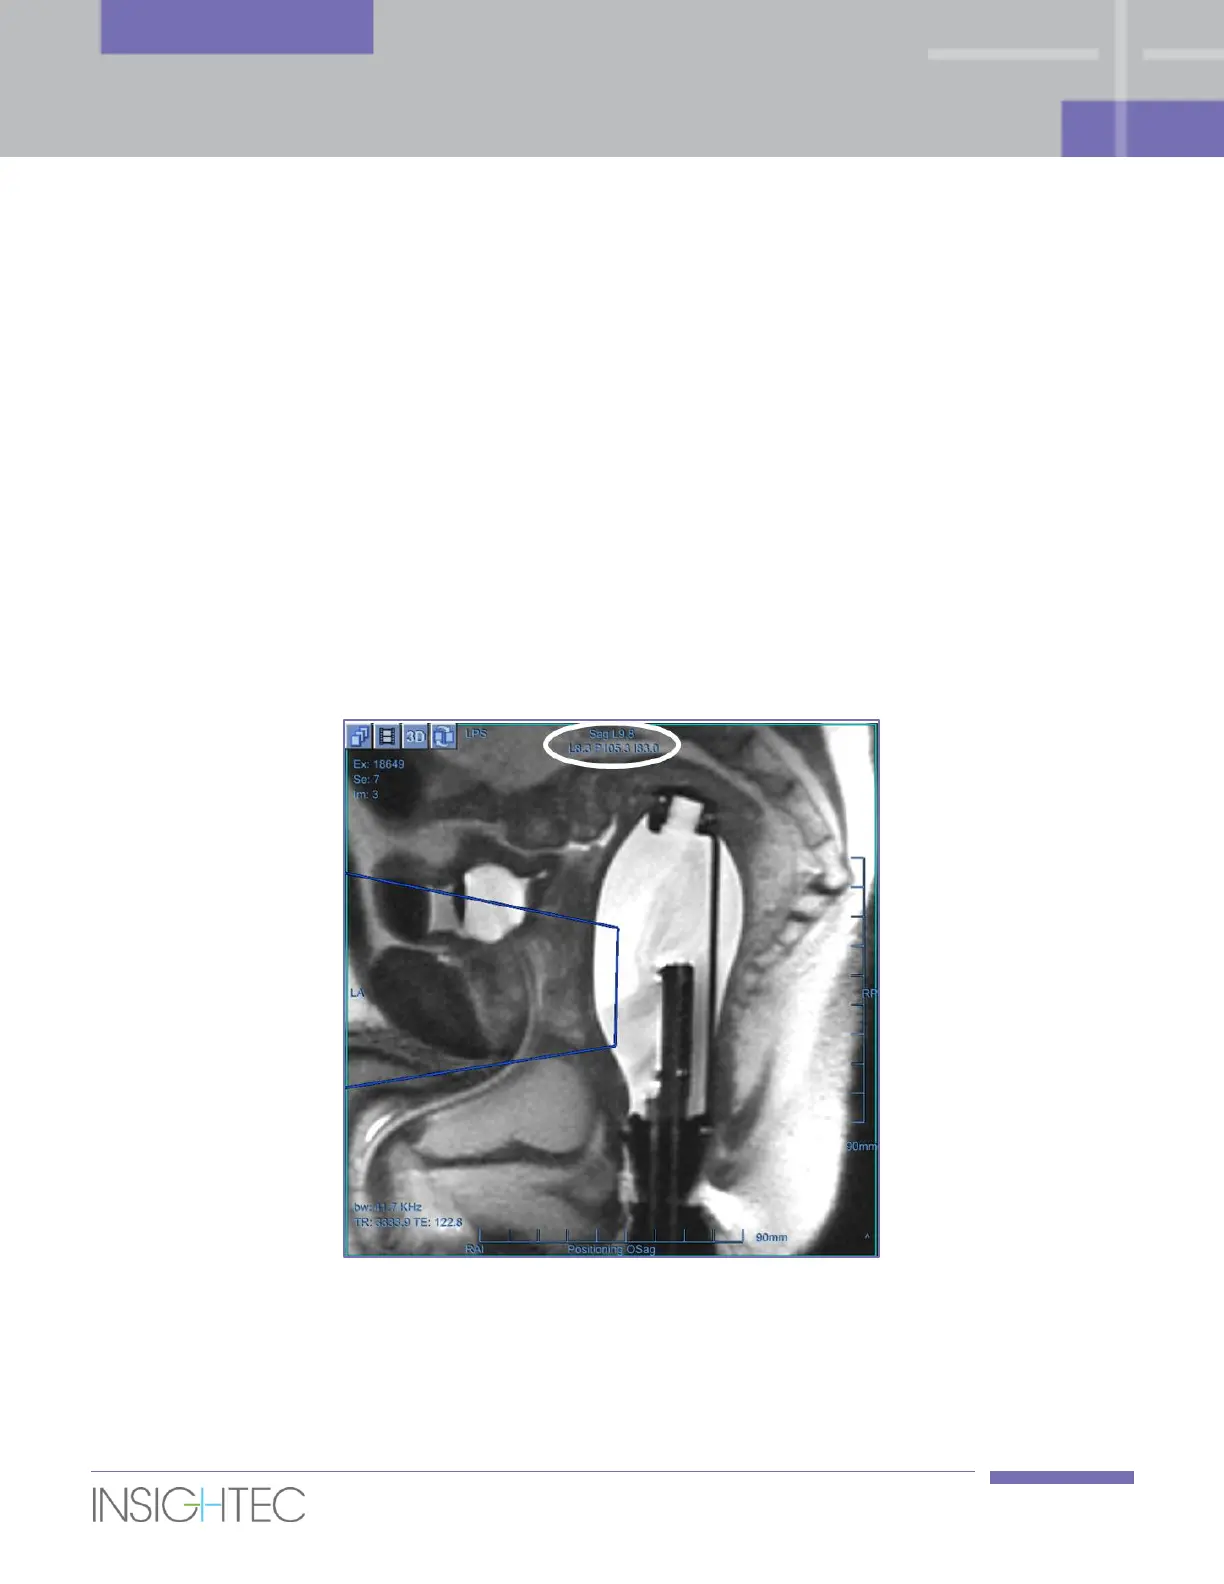

5.2.10.2. Cursor Coordinates

The cursor coordinates show the location of the anatomical feature pointed in three axes on all image

windows.

Figure 5-3: Cursor Coordinates